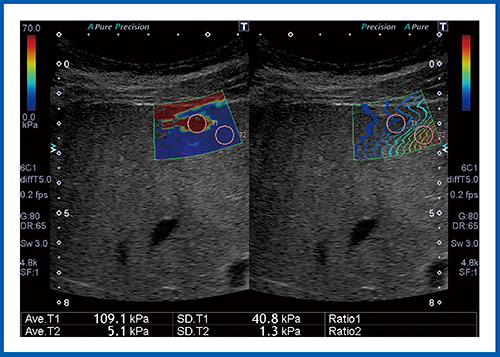

図8は,肝血管腫の症例である。赤く表示されている結節の弾性率は109.1kPaとなっており,値だけを見ると悪性腫瘍が疑われるが,ほかの画像も併せて読影することで,肝血管腫であると診断できた。

図8 肝血管腫のSWE